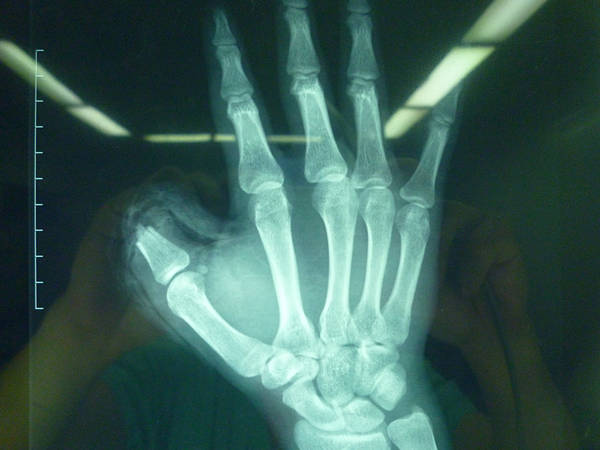

今天做的全型拇再造后供区修复的一种新方法

1个游离骨皮瓣+1个拇甲瓣+游离关节移植+1个全形再造+2处动静脉脉吻合=拇指再植。

好久没发帖了,今天刚刚做的!供区是新的修复方式!谢谢讨论!